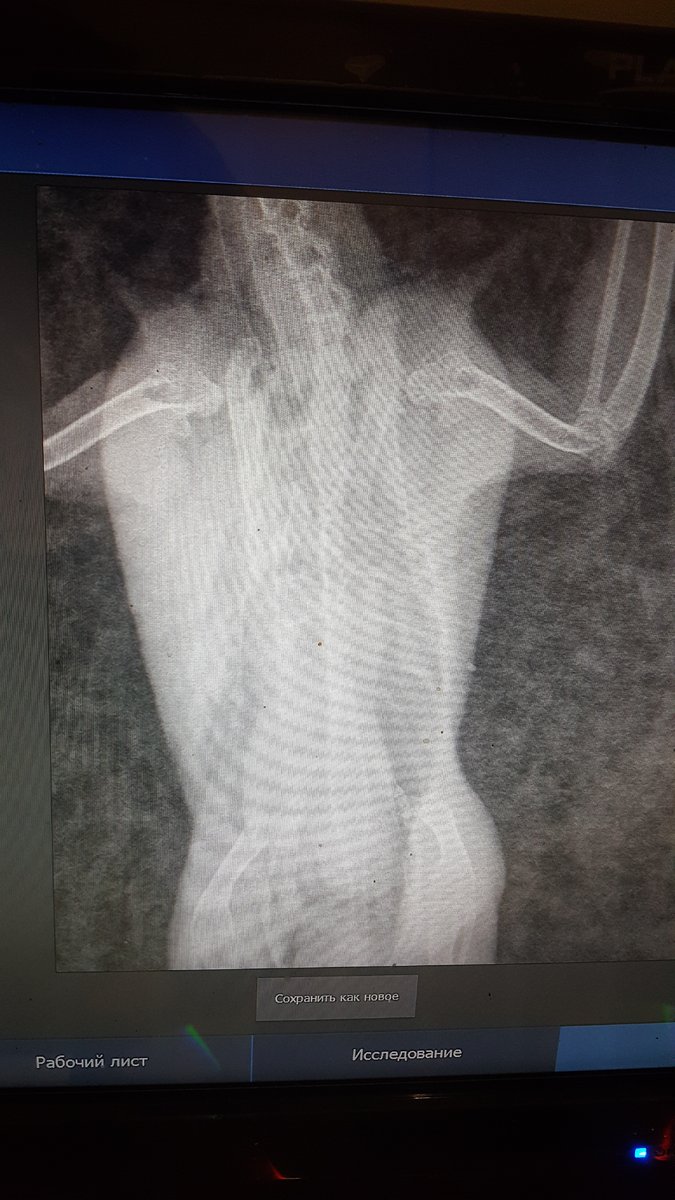

Pipka Опубликовано 18 апреля, 2020 Автор #73 Опубликовано 18 апреля, 2020 11.04.2020 в 21:10, Мария_К сказал: @Pipkaв надежде на хорошие новости от вас. @Мария_К , И ура!!!! Они таки хорошие!!!!!!! Люди, народ, поздравьте нас с Ёршиком!!!!!!! Мы поправились!!!! Не надо больше уколов, мерзких гадких заворачиваний в полотенце и принудительных выпаиваний горьким лекарством. МЫ ЗДОРОВЕНЬКИЕ!!!!! Посмотрите какой у нас чистенький и светленький рентгенччииккккк!!!!!!! Никаких затемнений, никаких гранулем или остаточных швов на легких. В сравнении с тем что было - день и ночь. Даже мне стало понятно и видно все. Мы поправились. По клинической картине: чихов нет, хрипов-сипов нет, нос чистейший, морду не трет, головой не дергает. Чуть позже выложу ввидео с ним. Пока вот рентген. Господи, как же я счастлива!!!!! Про липому все также. Без изменений. Но нам сказали что это фигня. Если будет правильно питаться и двигаться то больше чем есть не вырастет...

Pipka Опубликовано 18 апреля, 2020 Автор #74 Опубликовано 18 апреля, 2020 Извините, полосы - это мерцание на компе от телефона. Мне так не терпелось, что я прямо с компа на телефон щелкнула. а так ответ на диске, а у меня дома дисковода нема.